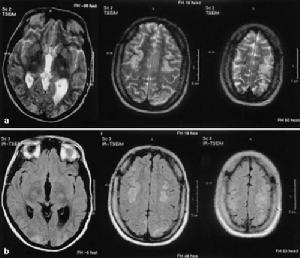

兩側半卵圓中心側腦室旁深部腦白質呈不甚對稱的長T1WI長T2WI信號,無占位效應,在T1WI圖像上呈低信號,T2圖像上呈高信號,全部病人腦室擴大,腦溝增寬,腦池擴大,表現為腦萎縮特徵。78例(89.6%)為多發性腦梗塞,9例(10.3%)為單發性腦梗塞,其中6例(6.9%)伴出血灶,男2例,女4例,其13例(14.9%),CT未發現腦梗塞,由MRI明確診斷。主要是對腦內脫髓鞘改變的範圍和腦萎縮的程度,特別是塞灶的大小,部位,腦缺氧早期診斷是否合併出血,這樣,對患者確定治療方案及預後有著深遠的意義。

影像學表現:CT表現為斑片狀及斑點狀低密度影,MRI表現為點狀及片狀長T1WI長T2WI信號,由腦深部灰質團塊萎縮,胼胝體繼發變薄,致使腦室擴大,又由於瀰漫性髓鞘脫失而有不同程度的腦萎縮,顯示腦溝增寬,腦池擴大(如圖1~4)。有高血壓及動脈硬化的病理基礎也可發生腦出血是腔隙性梗塞的直接原因。

賓斯旺格病診斷及鑑別診斷:CT,MRI的問世,為本病的生前診斷提供了影像學依據,CT表現為雙側腦室旁白質區與半卵圓中心顯示散在性或融合性低密度區,對稱或大致對稱,基底節,內囊與丘腦區可見多發性腔隙性梗塞,重者伴腦室擴大,其室管膜面多參差不齊,呈碎布狀。MRI表現:在腦室周圍白質與半卵圓中心顯示散在或融合性病變區,T1WI呈黑色,T2WI呈白色。重度與中度顯示腦室擴大,腔隙性梗塞顯影清晰,病灶數目比CT發現的多。SAE應與多發硬化,嚴重腦積水所致的室管膜水腫,CO中毒腦水腫期,腦囊蟲病腦炎型,ALZHEIMER氏病,PICK病,及其他特異性腦白質病,這些腦白質病變根據CT,MRI的表現特點,結合臨床表現60歲以上潛隱起病,逐漸加重,若具備卒中發作,高血壓,慢性進行性痴呆三大臨床特徵,綜合分析,即可做出診斷,也可隨訪複查。